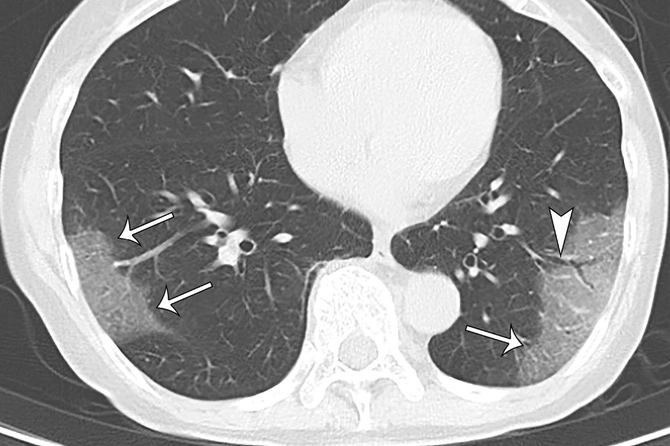

Сообщается, что 76 человек из 104 заболевших на лайнере перенесли болезнь бессимптомно. При этом у 41 человека из числа пациентов без симптомов обнаружили «эффект матового стекла» — своеобразные поражения тканей легких.

Исходя из этих данных, японские исследователи сделали вывод, что и при бессимптомном течении болезни легким наносится вред.